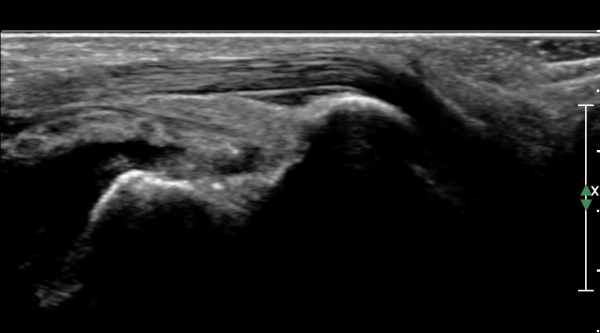

¹ß¸ñ ¿ÜÃø Ⱦ´Ü¸é(ºñ°ñ°Ç Ⱦ´Ü¸é)°Ë»ç¿¡¼­ ºñ°ñ°Ç ½ÉÃþÀÇ ´Ù·®ÀÇ ¼ö¾×Àú·ù°¡ °üÂûµÈ´Ù

(»çÁø 5, 6).